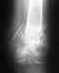

Врач связал с этим, хотя точно неизвестно. Делали массаж пер ректум(проктолог делал 3-4 сеанса), не особо помогло. Обезбаливающие дают побочку на кишечник((( рентген делали, врача там ничего не смутило, т.е. никаких изменений. Боли возникаю в основном после поездок или сидения на одном месте долгое время. Посоветуйте к кому обратиться(к какому врачу)..И что жет быть?